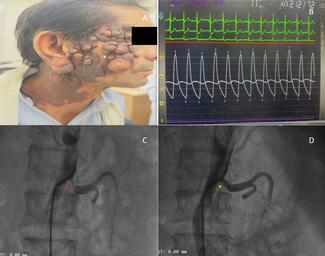

A 25-year-old man presented with 3 episodes of flash pulmonary edema in the past 2 months. Despite being on 4 antihypertensives, his blood pressure was 200/140 mm Hg. His serum inflammatory markers (erythrocyte sedimentation rate and C-reactive protein) were raised.

Computed tomography angiography of the abdomen revealed bilateral renal artery stenosis with 99% stenosis in the right renal artery and 90% stenosis in the left renal artery, with thickening of the abdominal aorta (Figure B) and the “double ring sign” (Figure A). A diagnosis of Takayasu arteritis type IV was made. Renal angiography confirmed the findings (Figure C and E) and, subsequently, the patient underwent bilateral renal angioplasty with a cutting balloon and a drug-coated balloon. The end result of the procedure was satisfactory with mild residual stenosis (Figure D and F) and a significant improvement in blood pressure. The patient was well controlled on a single antihypertensive at the 2-month follow-up.

Takayasu arteritis is an idiopathic, large vessel vasculitis affecting the aorta and major branches. It has the highest affinity for the left subclavian artery; however, in the Indian population, abdominal aorta involvement is more common. The “double ring sign” is an important sign and marker of active disease (showing a hyperenhancing outer ring due to thickening of the medial and adventitial layers due to inflammation, and a hypo-enhancing inner ring due to swelling of the intima and luminal narrowing). In light of ongoing disease activity and fear of stent restenosis in this case, stenting was deferred, and the patient underwent ballon angioplasty with acceptable results.